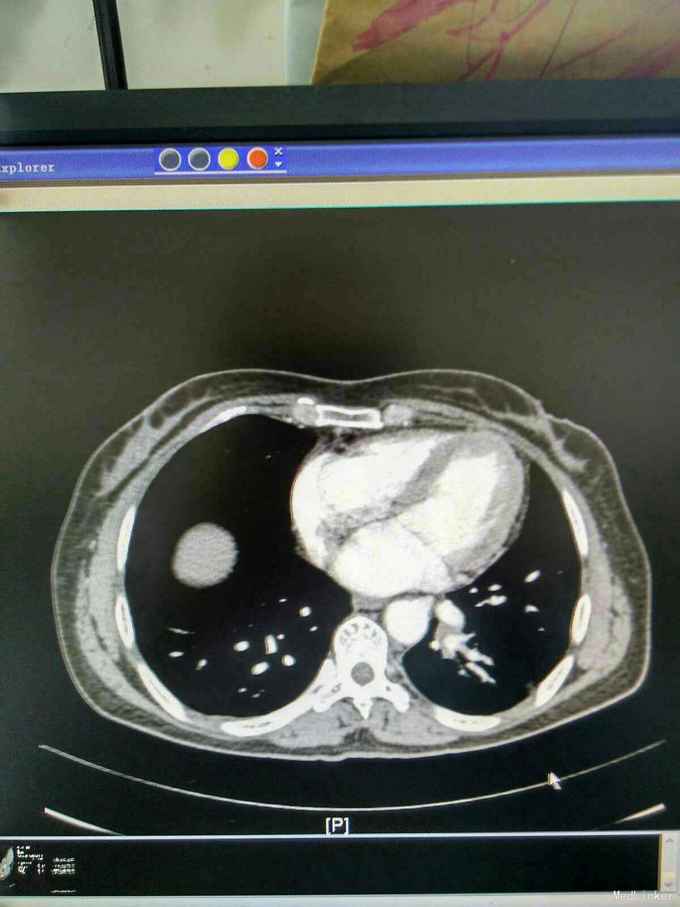

我院胸部ct增强,见左下肺病灶内见一异常供血血管,发自降主动脉,病灶周围见斑片状磨玻璃影。诊断为左肺下叶肺隔离症,转外科治疗。

患者外院胸部ct提示左下肺块影,原计划行ct引导下肺穿次活检术,我院胸部ct增强后发现,病灶为肺隔离症。遂转外科行左下肺切除术。